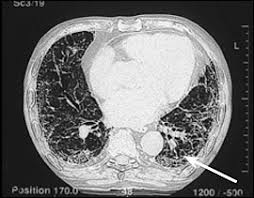

A Axial Ct Scan Of An Asbestos Exposed Person Shows A Left Sided Download Scientific Diagram

A Axial Ct Scan Of An Asbestos Exposed Person Shows A Left Sided Download Scientific Diagram from www.researchgate.net

A biopsy is the only definitive way to confirm a mesothelioma diagnosis. Advanced imaging offer much greater details and mris can help locate tumors significantly earlier than other scans. What you need to know. If you have worked and lived in connecticut for a significant amount of time, there is a chance that you were exposed to asbestos at home or in the workplace. Prior to 1980, most ships used asbestos insulation for piping and engine rooms. asbestos can be found in abundance in ships and shipyards. Connecticut light and power company was founded in 1917 by j. We report the ct findings of parenchymal and pleural diseases in a group of patients with a history of asbestos exposure, excluding lung cancer (which is not typical in this subjects) and asbestosis (which is a parenchymal fibrosis).

This fatal cancer usually doesn't manifest until 2 to 5 decades after the exposure to the asbestos, which necessitates specific expertise for these types of claims. At the moynahan law firm, our focus is on building long term relationships with our clients. Gould injury lawyers is a personal injury firm with offices in new haven and hartford, connecticut that serves clients throughout the state. Pleural effusions are typically hemorrhagic exudates of mixed cellularity but do not typically contain asbestos bodies. Since 1989, only one mesothelioma case in the state concluded with a jury verdict. Connecticut ranks 29th in the u.s. mesothelioma testing commonly includes imaging scans, biopsies and blood tests. These trust funds allow mesothelioma victims to recover compensation even after the company has filed bankruptcy. If you have worked and lived in connecticut for a significant amount of time, there is a chance that you were exposed to asbestos at home or in the workplace. Hannibal saldibar worked as a tile setter for 30 years, using mortar that contained asbestos. Connecticut light and power company ceased using asbestos products in facilities in the early 1980s. We report the ct findings of parenchymal and pleural diseases in a group of patients with a history of asbestos exposure, excluding lung cancer (which is not typical in this subjects) and asbestosis (which is a parenchymal fibrosis). Most diagnosed cases are pleural mesothelioma, which forms on the lining of the lungs.